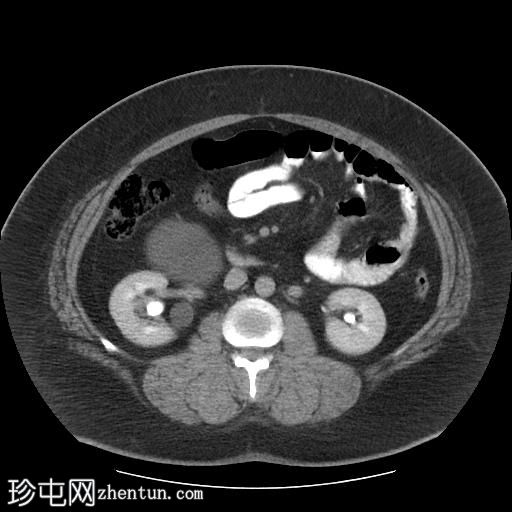

轴位

平扫

右肾集合系统完全重复。上肾集合系统的输尿管异位开口于前列腺尿道,导致上游集合系统显著扩张。这引起肾实质的慢性改变,包括上肾组织变薄和上肾盏排尿功能障碍。

相反,右肾下肾集合系统的输尿管位置正常,无扩张或结石迹象。

左肾和输尿管外观正常。